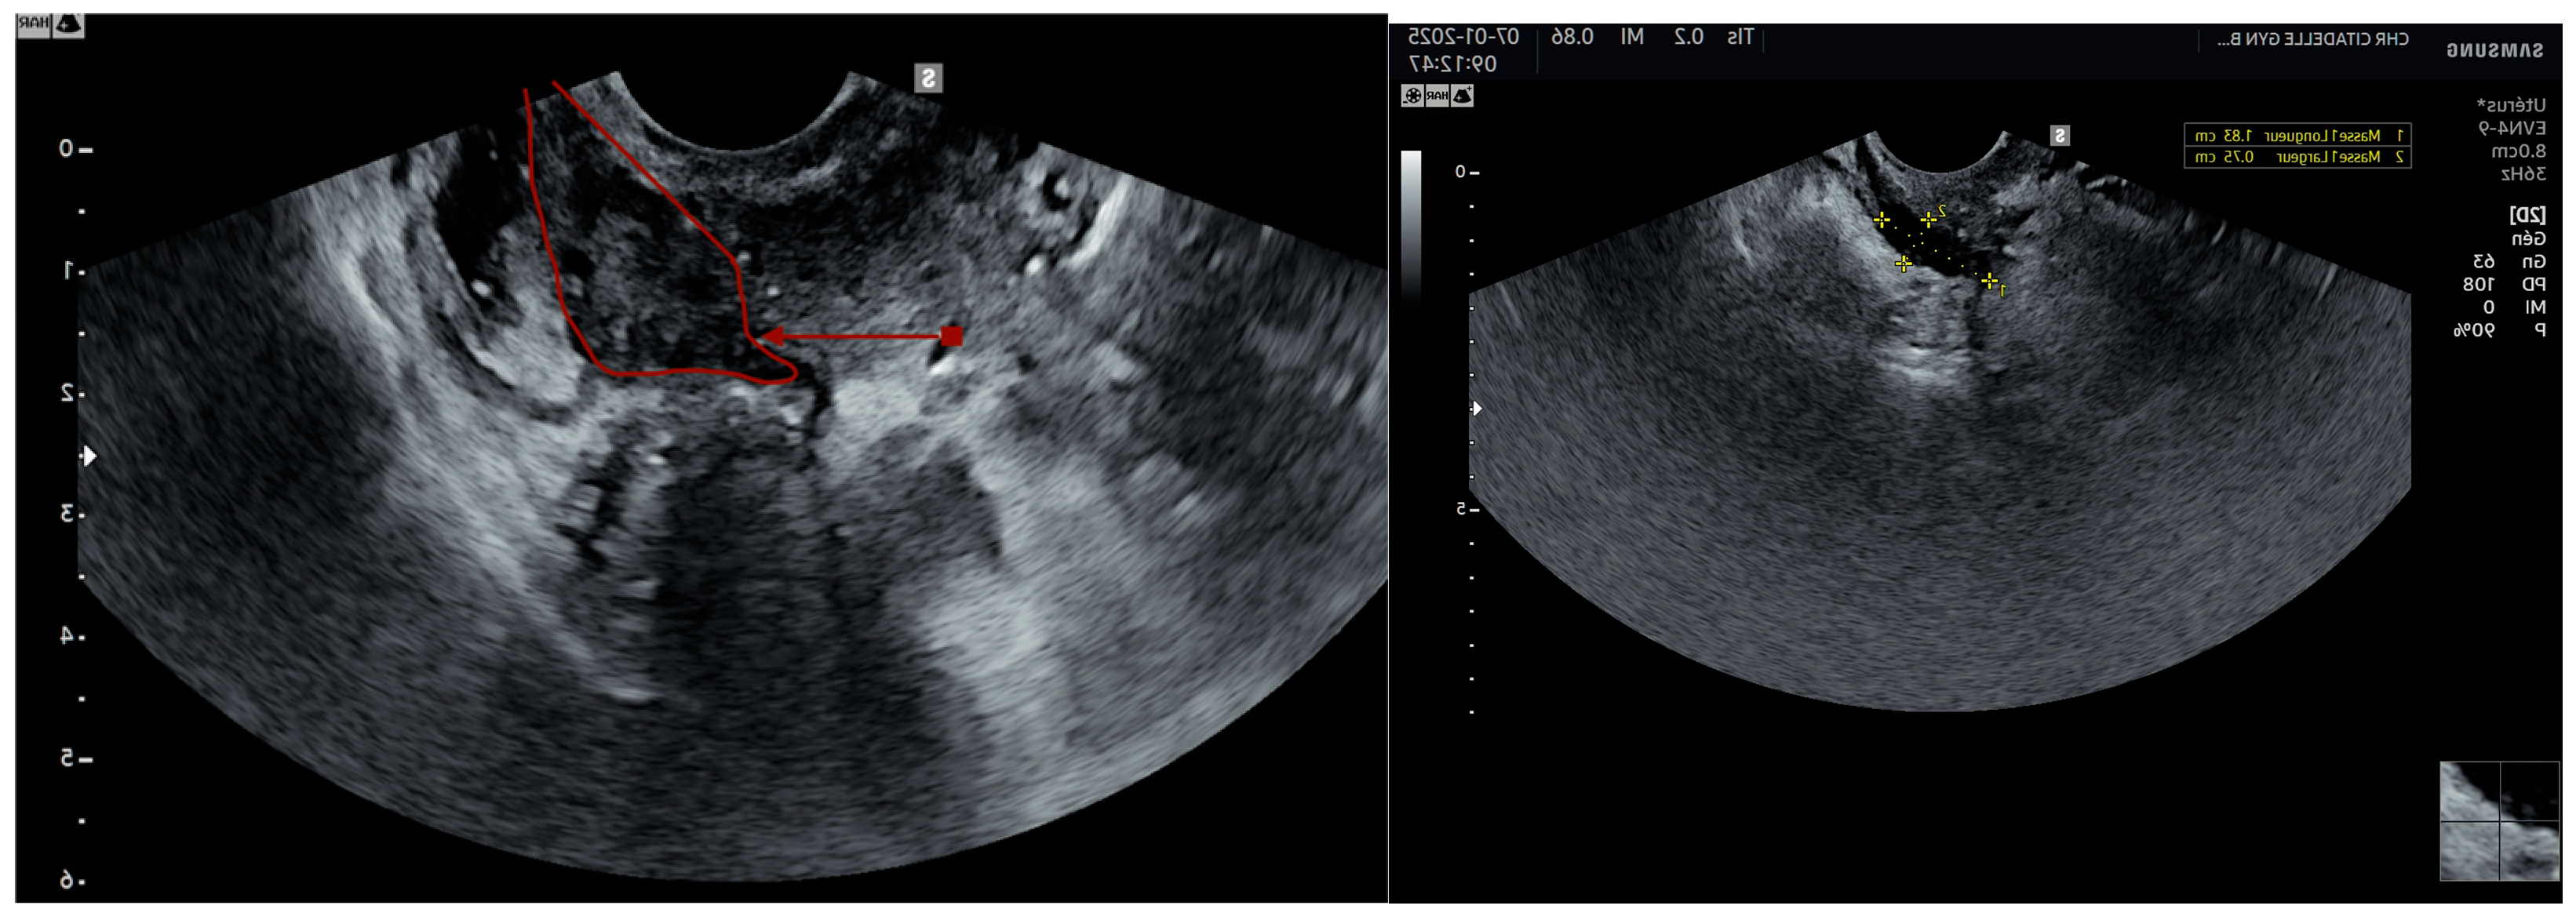

4. Ultrasound

- Endometriomas (number, size, kissing ovaries)

- Gently press against the cervix with the transvaginal probe to check if the anterior rectum moves smoothly across the posterior cervix (retrocervical area) and the posterior vaginal wall. If the anterior rectal wall glides freely, the sliding sign is considered positive for this region.

- To evaluate the posterior compartment, insert the probe into the posterior fornix.